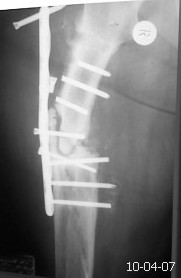

Травма в 2007 г. лечили больную консервативно. В 2009 г. у нас остеосинтез пластиной в сочетании с костной аутопластикой. Со слов больной после операции, дома в течение 6-ти месяцев соблюдала постельный режим,после чего начала ходить.Больная повышенного питания, сахарный диабет 2-го типа, неопрятна.Фотографию прилагаю. Планируем выполнить реостеосинтез пластиной с угловой стабильностью с повторной аутопластикой и пластикой по Хахутову.У кого какие мнения по поводу лечения?С уважением Никитин Константин

С учетом диабета однозначно оптимальный способ фиксации это закрытый БИОС, удаление м/конструкции малоинвазивный (вариант А.Н.) тем более гипертрофический ложный сустав (судя по снимку) в динамической версии БИОС должна сростись. Удачи.